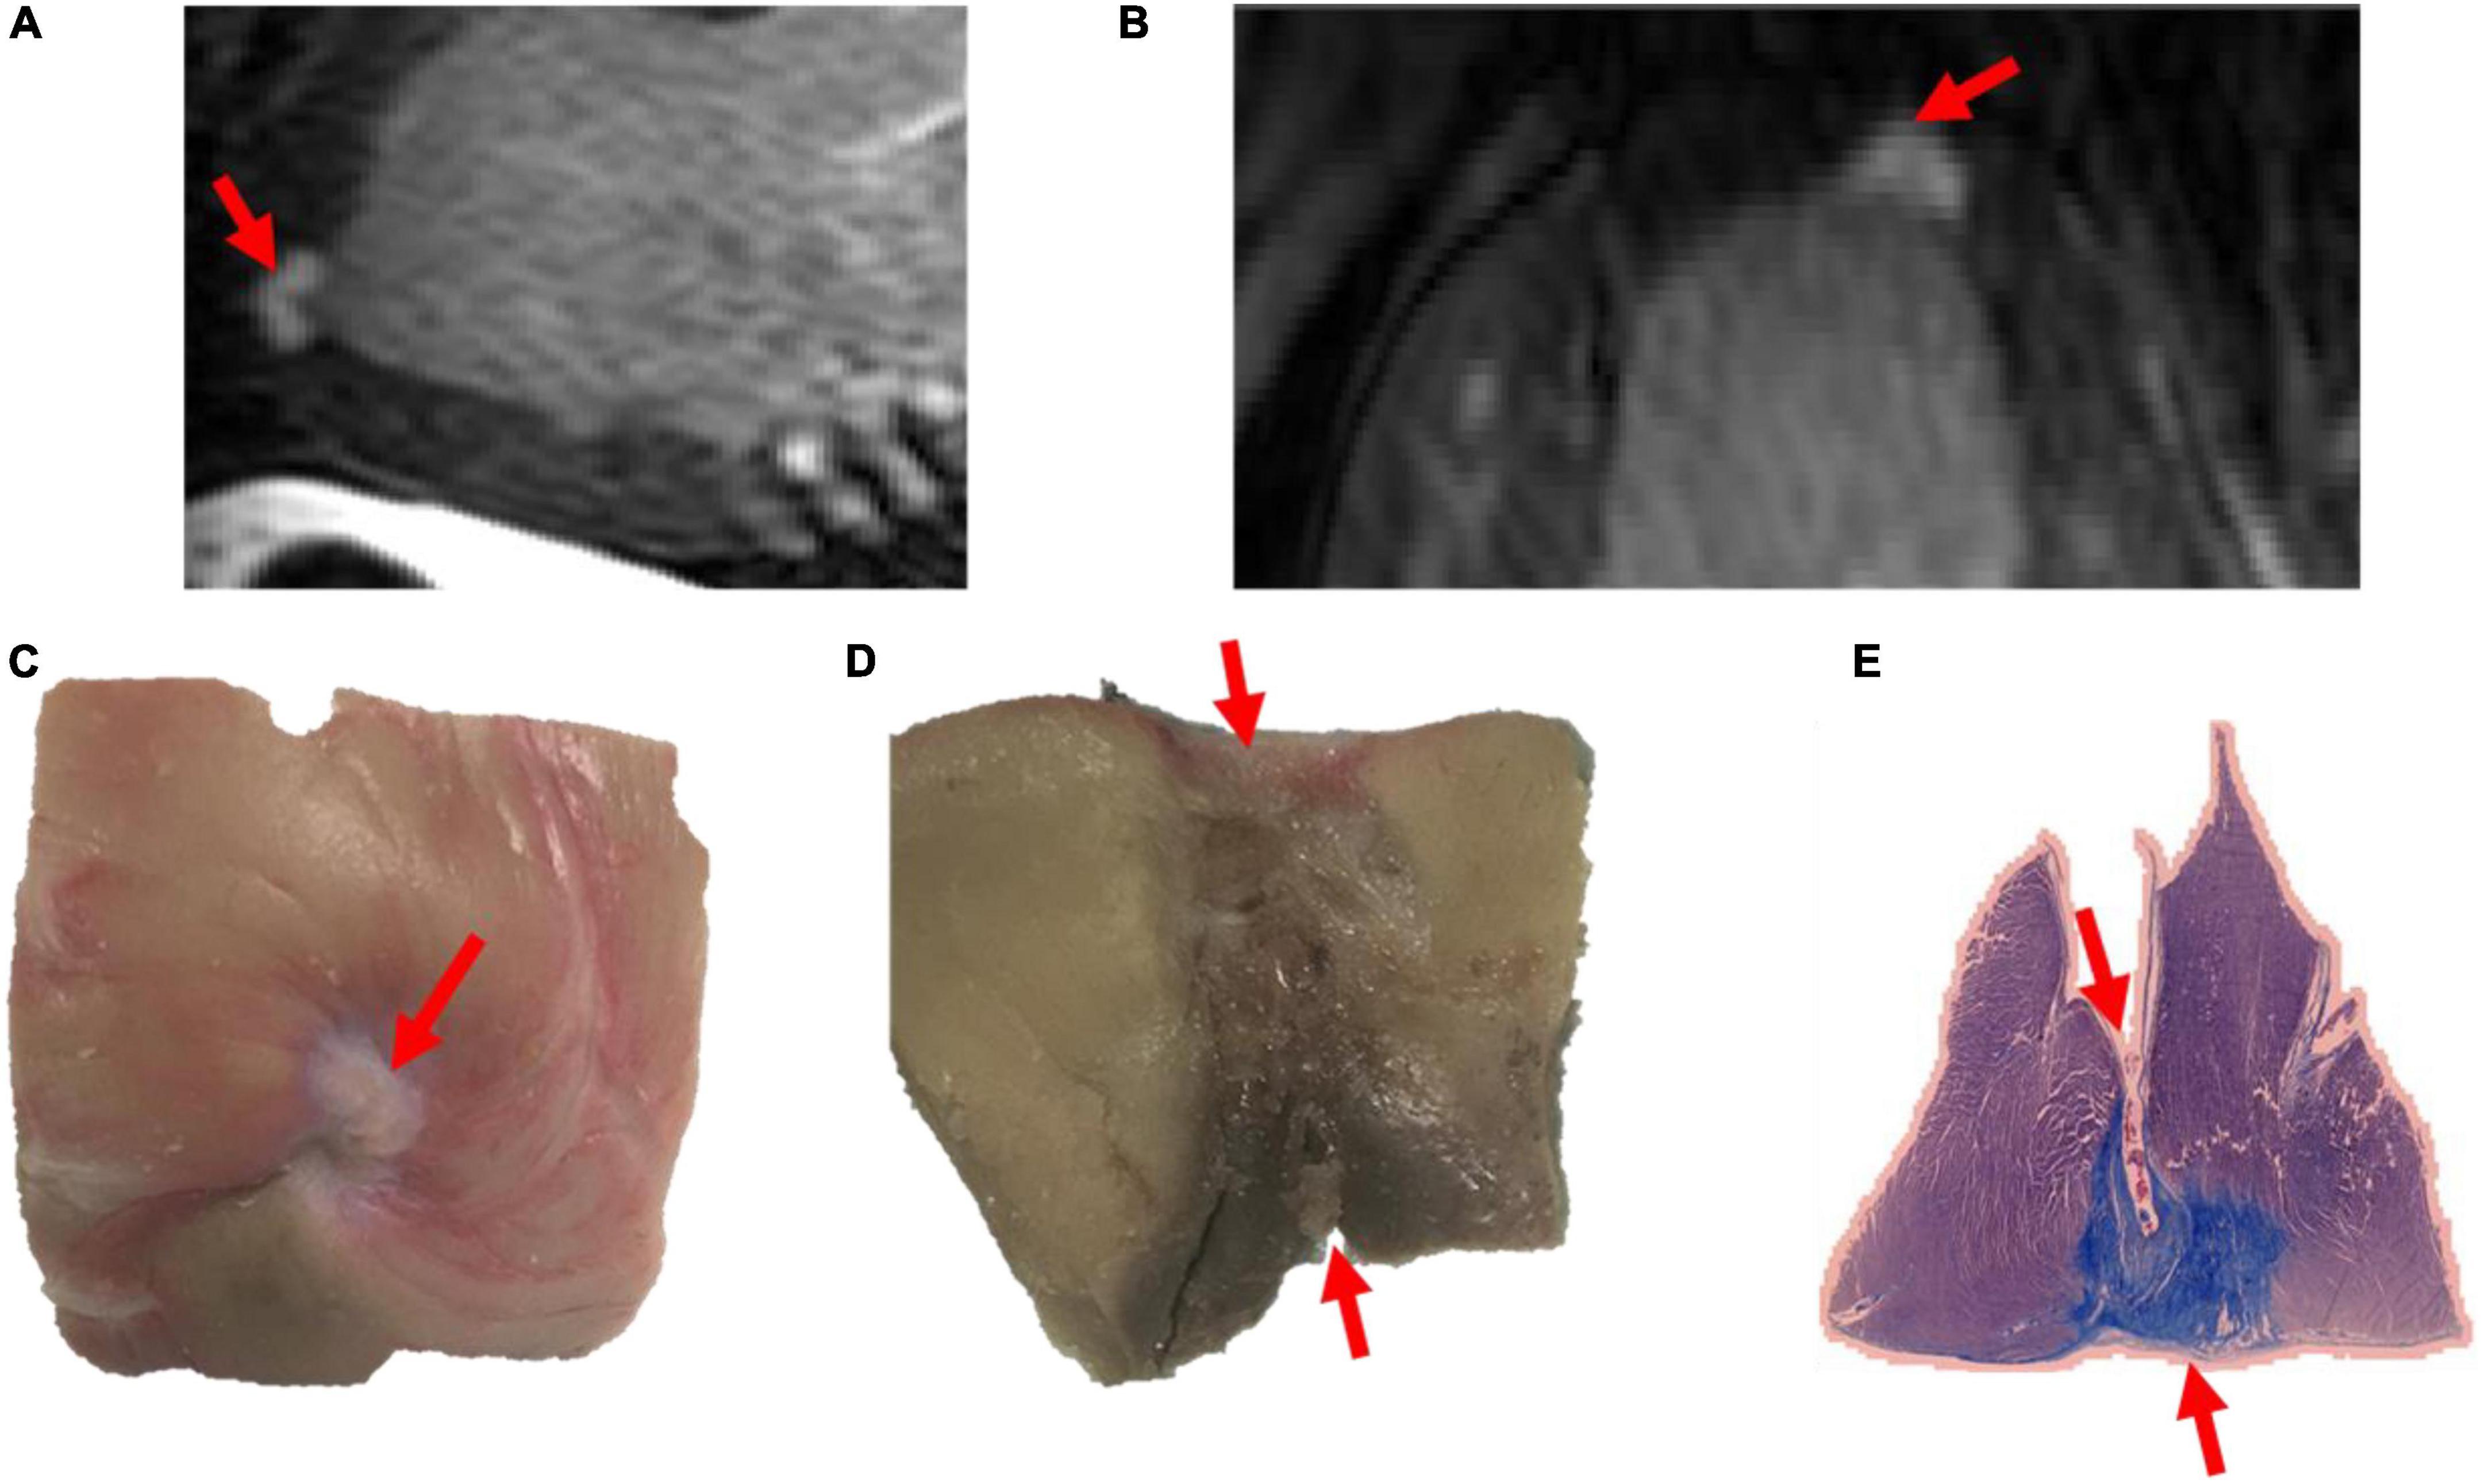

b- Data on transmurality after histological assessment

A total of 26 lesions were available for pathological assessment. Lesions were assessed pathologically after euthanasia for width, depth and transmurality. In terms of transmurality, lesions seen on LGE-MRI were very similar to lesions assessed on histology. Four lesions showed transmurality on LGE-MRI and 22 lesions were non-transmural. After pathological assessment by an operator blinded to LGE-MRI results, results were similar to those obtained on LGE-MRI: four lesions were transmural and 22 were not. Amongst the transmural lesions, two lesions were created in the RV free wall using 35W-30S and the two others were created in the LV apex using 50W-20S. Images of a transmural lesion are shown in Figure 3.

Figure 3. Images of a transmural lesion in the LV free wall on LGE-MRI [(A): sagittal view; (B): axial view] and pathology [(C): epicardial view; (D): axial view; (E): view on microscopy].

Out of the lesions available for pathological assessment, 15 were chronic lesions and 11 were acute lesions. In the acute lesions’ subset, 10 lesions were non-transmural on both LGE-MRI and histology and one lesion was transmural in both LGE-MRI and histology. Out of the chronic lesions’ subset as seen on LGE-MRI, 12 lesions were non-transmural both in the acute and chronic settings, and 3 were transmural both in the acute and chronic settings. On histology, 12 lesions were non-transmural, and 3 lesions were transmural.

c- Comparison between LGE-MRI lesions and pathological assessment post necropsy

The similarity between LGE-MRI and pathological assessment can be seen in Figure 4. Maximal lesion depth and width seen on histology as compared to LGE-MRI are summarized in Table 2. There was no statistically significant difference between histological findings and LGE-MRI measurements (p = 0.973 for width; p = 0.741 for depth).

Magnetic Resonance Imaging-Histology Lesion Size Comparison

There was a strong correlation between lesions seen on LGE-MRI and lesions assessed by histology as shown in Figures 3, 4. We have shown that ventricular ablation lesion size defined by MRI can be reliably associated with lesion size demonstrated by histological analysis (18). Dickfield et al. used a canine model to show that both T1-weighted (T1w) and T2-weighted (T2w) images were reliable in defining right ventricular ablation lesion size as seen on histology 12 h after the procedure. Though the T2w images were more consistent and showed higher signal intensity for the central necrosis zone compared to their T1w counterparts (19). Furthermore, the studies of Breen et al. (20) and Kholmovski et al. (21) also support the dependability of MRI in defining ablation lesion size as validated by histological specimen analysis.